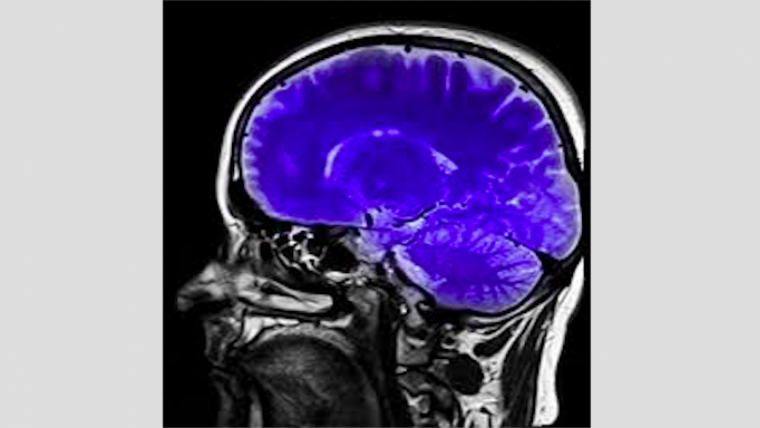

La resonancia magnética nuclear (RMN) es una prueba diagnóstica que emite imágenes del interior de nuestro cuerpo, llamadas “imágenes por resonancia magnética” (MRI por sus siglas en inglés).

Mediante esta prueba, el personal clínico puede detectar cualquier anomalía que no sea perceptible a simple vista o con otras pruebas, como la radiografía. La principal diferencia entre la resonancia magnética y la Tomografía Axial Computerizada (TAC), entre otras radiografías, es que la RM no utiliza radiación ionizante o rayos X.

Mientras la TAC genera imágenes por rayos X, la resonancia magnética emplea una serie de ondas de radio que atraviesan el cuerpo del paciente, el cual está expuesto a un potente campo magnético. Aunque ambas sirven para el diagnóstico de tumores, la primera es más utilizada para detectar lesiones internas y la segunda para detectar alteraciones congénitas.

Otra de las ventajas que presenta la resonancia magnética nuclear es que mediante su uso se pueden conseguir imágenes de alto detalle de cualquier punto y cualquier perspectiva del cuerpo; llegando incluso a obtenerse en dos o tres dimensiones.

No obstante, algunos centros disponen de máquinas abiertas adaptadas para personas con temor a verse encerrados. La imagen obtenida por resonancia magnética se denomina “corte”. En una sola prueba pueden obtenerse una gran cantidad de cortes, los cuales pueden almacenarse de forma digital o imprimir en papel.